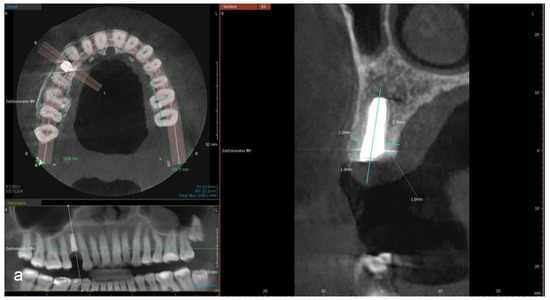

- a distance between the implant’s platform and buccal and palatal/lingual bone margin (dehiscence)

- thickness of buccal and palatal/lingual plates, 1 mm and 3 mm apically from the implant’s platform (perpendicular to the long axis of the implant).